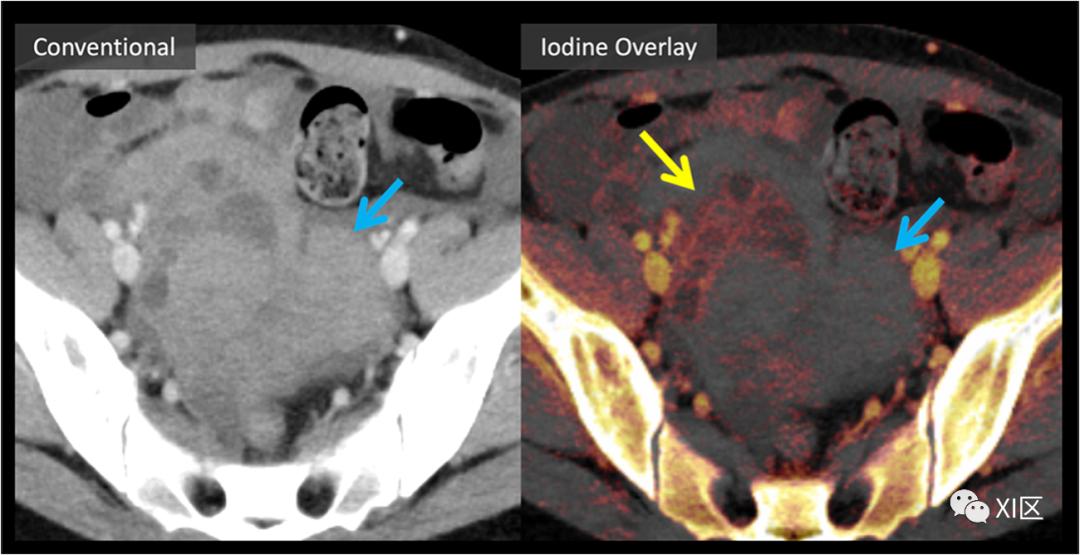

减少成像利用率和随访:DECT可以通过在最初检测时确定病理特征来减少对随访成像的需要

偶然性病变在常规腹部CT初始检查中是常见的,其原因与此无关。大多数常规的急诊科腹盆部CT检查都涉及一个门静脉期,这意味着许多偶然发现的病变在初次发现时不能完全表现出来。这通常会促使对后续成像提出建议,这会造成患者焦虑,可能会增加辐射剂量,增加下游资源利用率和医疗费用。在许多情况下,DECT能够全面描述偶发性病变,从而避免后续影像检查的需要。这对肾和肾上腺病变的评估尤其有希望。

肾损害评估与多囊肾

DECT碘选择性显像已被证明在根据病变内是否存在碘强化的基础上,有助于鉴别良性高密度囊肿和强化肾肿块。肾脏肿块评估通常包括多期肾脏肿块CT或MRI检查,包括平扫期、实质期和延迟期。由于扫描期相之间的错误配准限制了磁共振减影图像的应用,这些问题常常受到阻碍。然后,图像判读要求在手动放置的感兴趣区域中,在单独的、可能错误配准的扫描阶段对HU值(或MRI信号)进行比较。这对常染色体显性遗传性多囊肾病患者尤其具有挑战性,他们有更高的患肾细胞癌的风险,并且可能有比单纯液体衰减更高的多个病变。DECT可以简化多囊肾的评估,因为生成的碘含量本质上与VNC信息共同配准,如图7所示。这种方法已经被证明可以减少解释时间,并提高放射科医生对被评估的肾损伤中是否存在碘含量的信心。